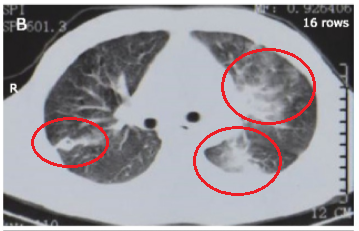

(第一次胸部CT)

应该是肺结核,医生分析说。

第一次没找到,于是留了第二次痰,第三次,第四次,多留几次痰,肯定能找到抗酸杆菌,毕竟患者的胸部CT看起来那么像肺结核,而且也有长期反复的发热、咳嗽、咳痰、胸痛,必须得是肺结核啊。